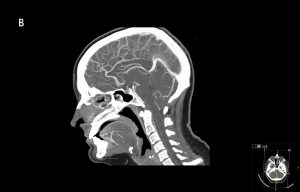

Riktade utredningar och behandlingar genomförs för de tillstånd som bedöms kunna föreligga. Endotrakeal intubation övervägs hos djupt medvetandesänkta patienter för att säkra luftvägen och skydda mot aspiration. Den traditionella intubationsgränsen är GCS ≤8, men intubation kan avstås vid snabbt reversibla tillstånd eller vara indicerad vid GCS >8, till exempel vid tillstånd med förväntad försämring i medvetandegrad [34]. Förutom patientnära prov tas prov på leukocyter och trombocyter, koagulationsstatus, CRP, leverenzymer [34] och totalt CK/myoglobin om rabdomyolys kan föreligga. Urintoxikologiskt prov ger ofta falskt positiva och negativa svar som vilseleder den diagnostiska processen och rekommenderas därför inte [75-77]. Urinretention upptäcks med ultraljud. Vid misstänkt strukturell orsak beställs DT hjärna. Vid misstänkt dissektion, basilarisocklusion eller venös sinustrombos beställs även DT-angiografi/-venografi av halskärl och intrakraniella kärl. Vid misstänkt status epilepticus beställs akut-EEG för att utesluta fortsatt subklinisk anfallsaktivitet [78].